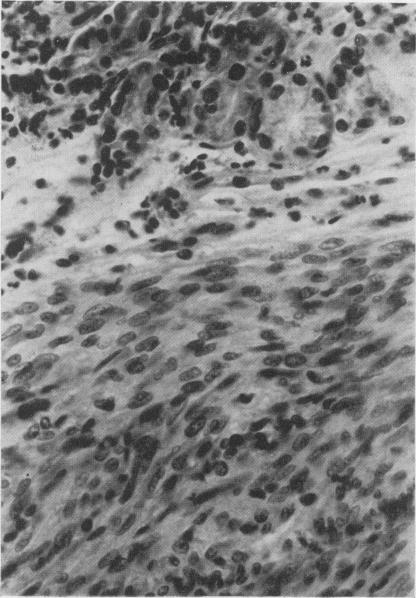

Five patients with smooth muscle tumours of the stomach are presented. In 3 cases, histological identification of the lesion was made pre-operatively on biopsy material obtained under direct vision at gastroscopy.

本文报告了5例胃平滑肌肿瘤患者。其中3例在术前通过胃镜直视下获取的活检材料进行了病变的组织学鉴定。